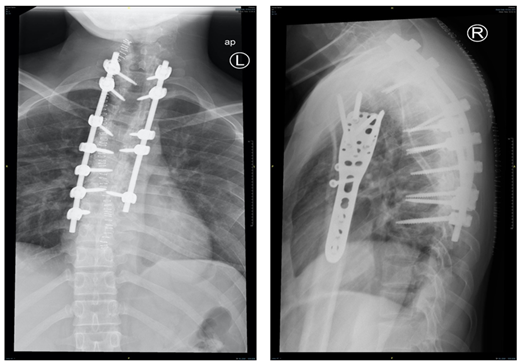

A 26-year-old male, soldier, involved in road traffic accident on 27th of August 2019 in the southern region of Saudi Arabia. The patient was transferred to the military hospital in the south and they stabilized him there and then transferred to our hospital on 29th of August 2019. The patient had multiple injuries: T3–T4 spinal fracture (Figure 1), left proximal humerus fracture (Figure 2), 8th & 9th rib fractures with multiple lacerations. He underwent for left open reduction and internal fixation of the proximal humerus by using Proximal Humerus Internal Locking System "PHILOS" plating on 03-Sep-2019 (Figure 3A & 3B). Also, the patient underwent spinal fixation for the fracture from T1 to T8on 05-Sep-2019 (Figure 3C). One month postoperatively, he started to have left big toe gangrene and vascular surgery was consulted. They recommended doing CT angiogram of the aortic arch and echocardiogram. CT showed that left pedicular screw of T6 and T8 appear lateral to the pedicle and the tip of the screws abutting the medial wall of the descending thoracic aorta at the posterior mediastinum but there is no obvious surrounding active haematoma or aortic thrombosis (Figure 4A & 4B). Pre-operative assessment and measurement were done and it was showed: Whole length supposed to be covered: 10cm, Proximal landing zone on the sagittal view: 2.67cm, Distal landing zone on the sagittal view: 1.83cm, Proximal axial: 2.14cm x 2.11cm, and distal axial: 1.92cm x 1.78cm.

Figure 1 MRI sagittal cut of cervical and dorsal spine showed a compression fracture of T3 vertebral body with 50% reduction in its height and compression fracture of T4 involving only the superior endplate with retro-pulsed posterior vertebral margin of T3 causing cord contusion.

Figure 3 Anteroposterior (AP) & lateral views of left humerus, post open reduction and internal fixation by PHILOS plate (05.Sep .2019) [A&B ], with posterior spinal instrumentation from T1 -T7 [C].